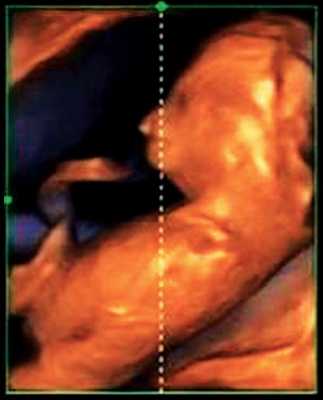

Гипоплазия нижней челюсти при различных нехромосомных синдромах обычно встречается в сочетании со скелетными дисплазиями и мышечно-скелетными аномалиями: синдром Пьера Робена (рис. 3), Тичера - Коллинза (Франческетти), акрофасциальный дизостоз, цереброкостомандибулярный синдром, ахондрогенез (рис. 4), ателостеогенез, кампомелическая дисплазия, диастрофическая дисплазия (рис. 5), синдром множественных птеригиумов, синдром Пены - Шокейра и др. Наличие микрогнатии характерно для синдрома Карпентера, синдрома Фринса, синдрома Меккеля - Грубера, гидролетального синдрома, синдрома Миллера - Дикера, синдрома Нунан, синдрома Секкеля, Рубинштейна - Тейби и др. Большинство из описанных синдромов имеют аутосомно-рецессивный либо аутосомно-доминантный тип наследования [10, 11].

Рис. 3. Микрогнатия у плода при синдроме Пьера Робена в 13 нед беременности.

Рис. 4. Микрогнатия у плода с ахондрогенезом в 13 нед беременности.

Рис. 5. Микрогнатия у плода с синромом диастрофической дисплазии в 12 нед беременности.